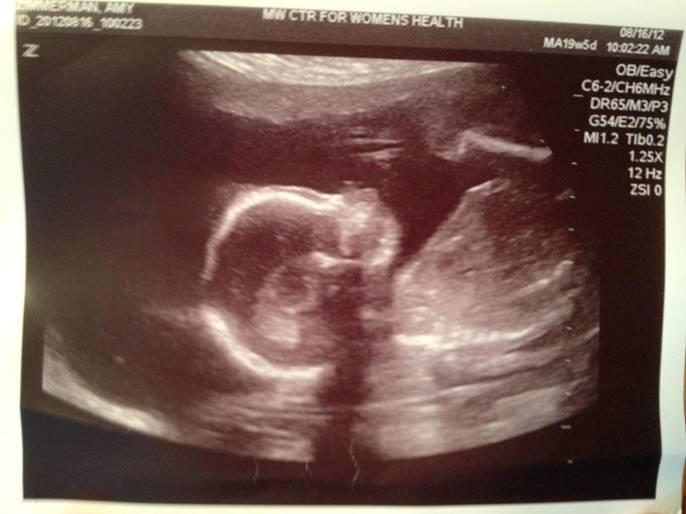

Woohoo! Week 20 – the half way mark and I am very happy to announce that we are having another little girl! Miss Macklynn Elizabeth Zimmerman will joining our crazy lives in (hopefully, but I learned my lesson the first time) 20 weeks! I have to say, I called it the night before our ultrasound because my husband put his hand on my belly to feel her move for the first time. She started going crazy when she’s usually very calm for me. I thought to myself, “oh GREAT! Another daddy’s girl!” Sure enough, after a lot of persuading, she allowed us to see that she’s a girl.